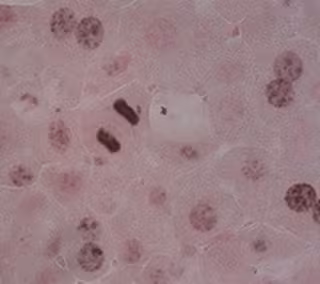

Investigadores del Hospital Universitario de Salamanca, de la Universidad de Salamanca y del Instituto de Investigación Biomédica de Salamanca colaboran con el Centro Nacional de Investigaciones Cardiovasculares en la identificación de una proteína relacionada con el estrés que "podría convertirse en una nueva diana farmacológica para el cáncer de hígado".

Así lo ha señalado el Instituto de Investigación Biomédica de Salamanca (Ibsal) sobre "una proteína relacionada con el estrés podría convertirse en una nueva diana farmacológica para el cáncer de hígado, un tipo de tumor para el que actualmente hay pocas opciones farmacológicas".